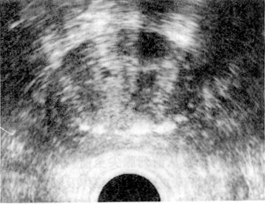

摘要 为探讨良性前列腺增生症(BPH)腔内B超特征及超声所测定量指标与手术切除标本重量间的相互关系,对563例BPH患者进行了经直肠B超检查,测定整个腺体及移行带体积并与45例手术标本行相关回归分析。结果发现:BPH有其特有声像特征,移行带体积与手术标本重量值呈显著相关性(r=0.988,P<0.001,误差为4%);腺体体积与手术标本重量值间也成直线相关性,但误差达47.8%。使用多平面高频7.5MHz探头的经直肠B超可以准确估计前列腺及增生腺体的大小,前列腺区带的定量学研究对减少超声误差,指导BPH诊断及治疗十分重要。